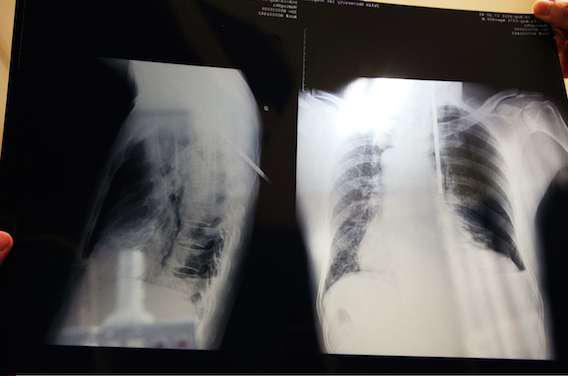

Premier espoir de traitement dans la mucoviscidose. Une thérapie génique inhalée permet de stabiliser les symptômes pulmonaires de la maladie. Les résultats d’un essai clinique de phase II sont publiés dans le Lancet Respiratory Medicine. Les malades ont inhalé pendant un an une solution permettant de remplacer les gènes défectueux responsables de la maladie.

Les chercheurs ont régulièrement évalué la fonction pulmonaire des participants en mesurant le volume d’air exhalé en une seconde. Au bout de deux ans, l’amélioration est plus marquée de 3,7 % chez les volontaires sous thérapie génique par rapport au groupe placebo. D’après le Pr Stephen Hyde, co-auteur de l’étude, c’est davantage le résultat d’une stabilisation de la mucoviscidose que d’une réelle amélioration. Mais « la stabilisation de la maladie pulmonaire est un objectif en soi. Nous poursuivons d’autres études sur des thérapies géniques non virales, avec différentes doses et combinaisons médicamenteuses et des vecteurs plus efficaces. »